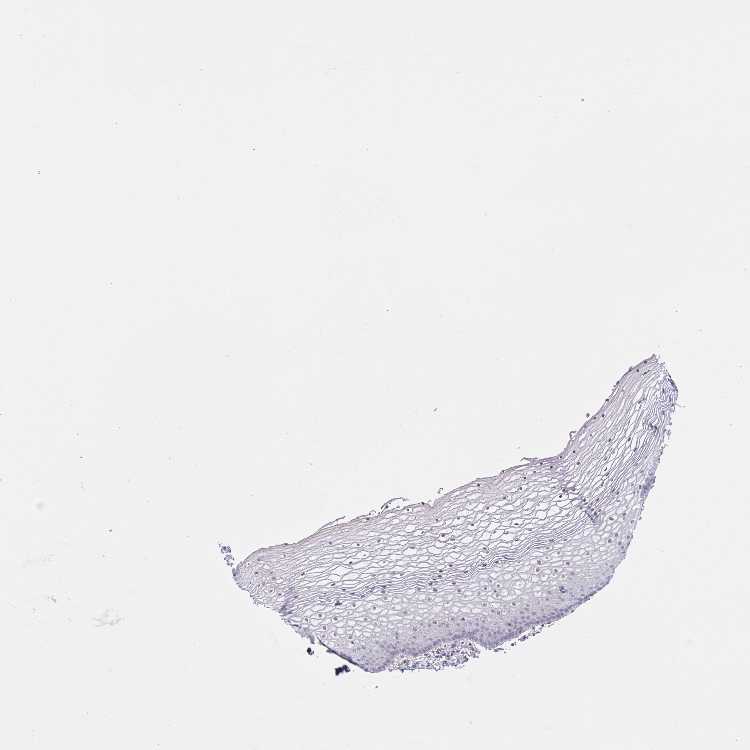

TISSUE PRIMARY DATA VAGINA Show tissue menu

VAGINA - Antibody stainingi

Antibody staining in the annotated cell types in the current human tissue is reported as not detected, low, medium, or high, based on conventional immunohistochemistry profiling in selected tissues. This score is based on the combination of the staining intensity and fraction of stained cells.

Each image is clickable and will lead to virtual microscopy that enables deeper exploration of all samples and also displays staining intensity scores, fraction scores and subcellular localization as well as patient and tissue information for each sample.

Antibody HPA058361Antibody HPA059572

Squamous epithelial cells LowNot detected